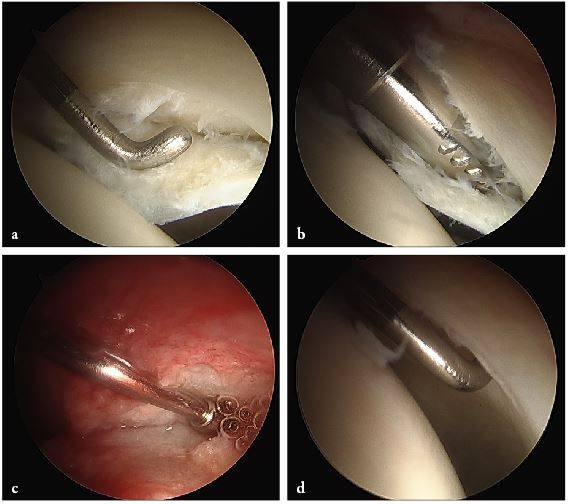

Visualisation of the central compartment of the joint for chondral and labral lesions is performed arthroscopically. After having applied distraction of the leg a 3.5 mm arthroscope (70° optics) is inserted from the anterior incision. Fluid management as in normal arthroscopy with continuous flow allows proper visualisation. The anterosuperior and lateral parts of the acetabular labrum with the adjacent articular cartilage and the femoral head are inspected. These are the areas where most of the relevant labrum and cartilage lesions are located. Depending on the amount as well as type of damage, reconstructive procedures are performed with and without traction. Ossified or ruptured parts of the labrum are resected or refixation of a partially detached labrum is performed with resorbable suture anchors (fig. 4a and 4b). Refixation of debonded cartilage flaps (fig. 5 a–d) curettage and microfracturing of damaged cartilage fragments and even autologous chondrocyte transplantation is possible (Bretschneider et al. 2020).

Contouring of the femoral head and neck by osteochondroplasty is performed with a partially covered acromionizer (fig. 6a and 6b).